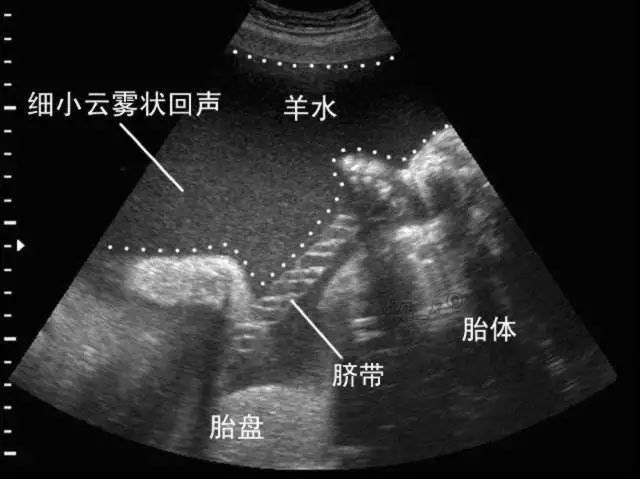

早期的羊水是由受精卵核分裂渗出的组织液形成的,中期由羊膜、胎盘、脐带渗出的组织液构成,到了怀孕5个月左右,羊水中又多了胎儿排出的尿液。

羊水可以保护胎儿,当妈妈的腹部受到外来的压力和冲击时,羊水可以起到一个缓冲的作用,避免和减缓胎儿受到伤害。羊水中还有部分抑菌物质,这对于减少胎儿感染能起到一定作用。

孕妈妈平时在走路或者做其他动作时,因为胎儿是漂浮在羊水中的,所以不会被摇晃的很厉害,可以让胎儿的舒适度大大增加。

羊水的温度一般在38~39℃左右,并且很稳定,可以让子宫保持恒温,给胎儿提供一个温暖适宜的成长环境。

当胎儿不断长大,会经常伸伸胳膊、蹬蹬小腿,这时候羊水可以为胎儿提供充足的空间,避免空间局促而让胎儿的骨骼发育受到限制,防止胎儿肢体发育畸形。

在胎儿即将出生时,羊水会在胎儿的头前方形成前羊水囊,能起到扩张子宫颈的作用。

生产时,羊水还可以缓冲宫缩对胎儿造成的压力。同时羊水还有一定的润滑作用,可以使产道不过于干涩,更易于胎儿的娩出。